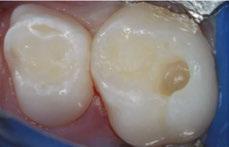

The 5-year-old patient featured in this case study did not benefit from early oral care and had multiple carious lesions. Considering the young age, high caries risk, and the uncertainty of compliance with follow-up appointments, I wanted to restore and seal all teeth in one visit. One quadrant is shown in this case study. The carious lesion on tooth J (65) was cavitated and prepared, restored, and sealed. Tooth I (64) was non-carious and would only be sealed (Figure 1).

surface of tooth I (64) was also lightly abraded with a diamond bur (Figure 2). The preparations were selectively etched with phosphoric acid, rinsed, and lightly dried (Figure 3). Bonding agent was applied to the entire occlusal surfaces of both teeth, air thinned, and light-cured (Figure 4).

Tooth J (65) was bulk-filled with Activa Kids. For this fast injection technique, I place the dispensing tip at the floor of the preparation and extrude the material without removing the tip until the preparation is completely filled (Figure 5). I like to do some minor manipulation of the filling material with hand instruments to create anatomy, as well as to ensure the material is flush with the surface of the preparation, and no air is trapped inside. Activa Kids is dual-cure, ideal for bulk filling, and can be cured with all lights. A thin topcoat of Activa Presto was placed as a sealant on the entire occlusal surface of teeth I and J (64 and 65) (Figure 6). Figure 7 shows the final clinical situation.

Figure 1 (left): Caries lesion on tooth J (65). Figure 2 (center): Preparation of tooth J (65) and abraded occlusal surface of tooth I (64). Figure 3 (right): Selective etch of enamel Figure 4 (left): Bonding agent is applied to both teeth I and J (64 and 65). Figure 5 (right): The preparation is filled with ACTIVA Kids Figure 6 (left): A thin topcoat of ACTIVA Presto is applied to the occlusal surfaces of teeth I and J (64, 65). Figure 7 (right): Final result